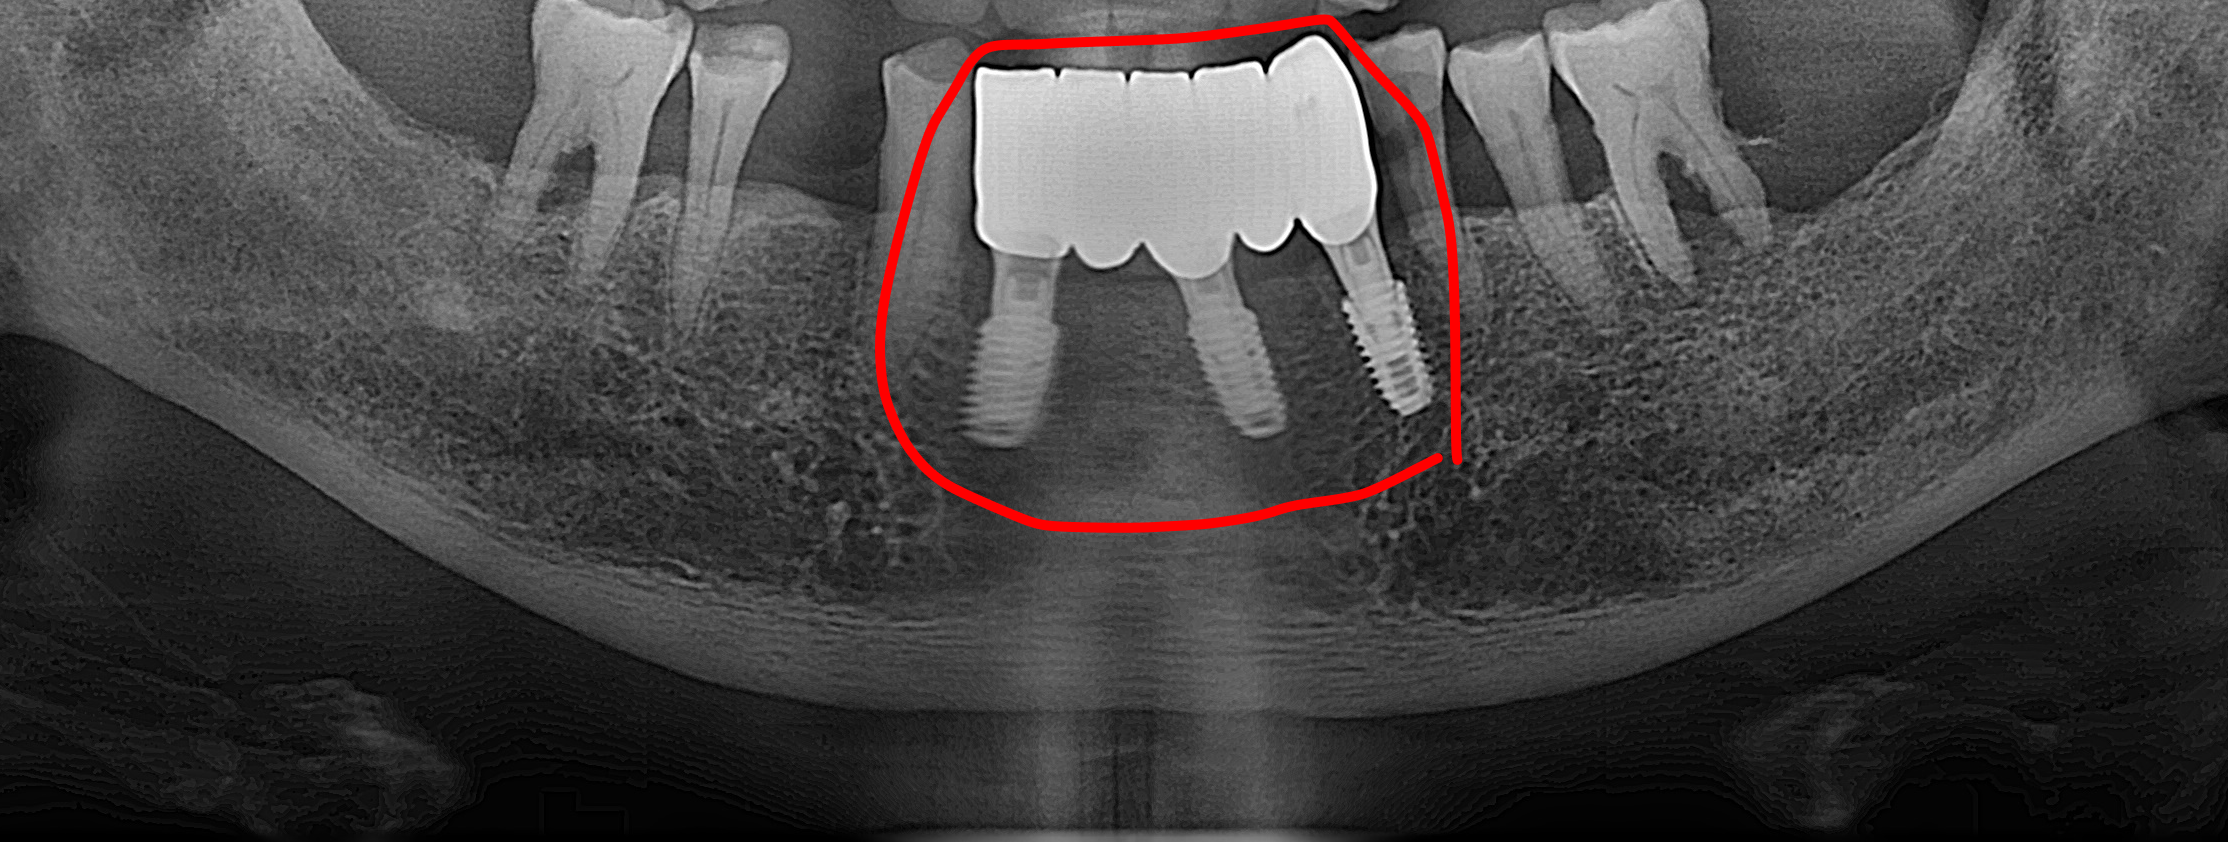

앞니는 대화하거나 웃을 때 가장 먼저 노출되는 부위이며, 식사의 첫 단계를 담당하는 중요한 치아입니다. 환자분의 우선순위를 존중하여, 1차적으로 하악 전치부에 임플란트 식립을 선행하였습니다. 이를 통해 환자분이 가장 크게 느끼던 심미적 결손과 앞니 저작의 불편함을 빠르게 해소하는 데 집중했습니다.

앞니 부위의 수술이 안정적으로 진행된 후, 어금니 저작 기능 회복을 위해 좌측 대구치 부위의 수술을 이어서 진행했습니다.